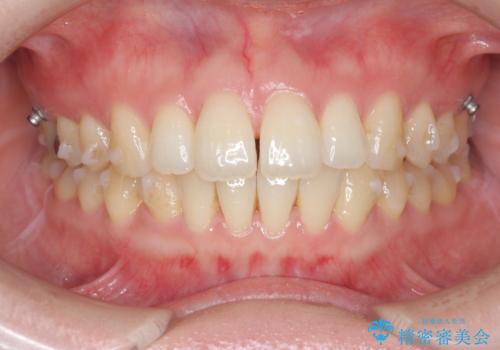

- 出っ歯に見える前歯を治したい、と矯正治療を希望され来院されました。

奥歯の噛み合わせに大きな問題はないので、目立つ前歯の角度・隙間を重点的に整え、審美的な歯並びを獲得できるよう計画します。

治療によりしっかりと前歯の角度が改善され、審美的な歯並びを手に入れることができました。